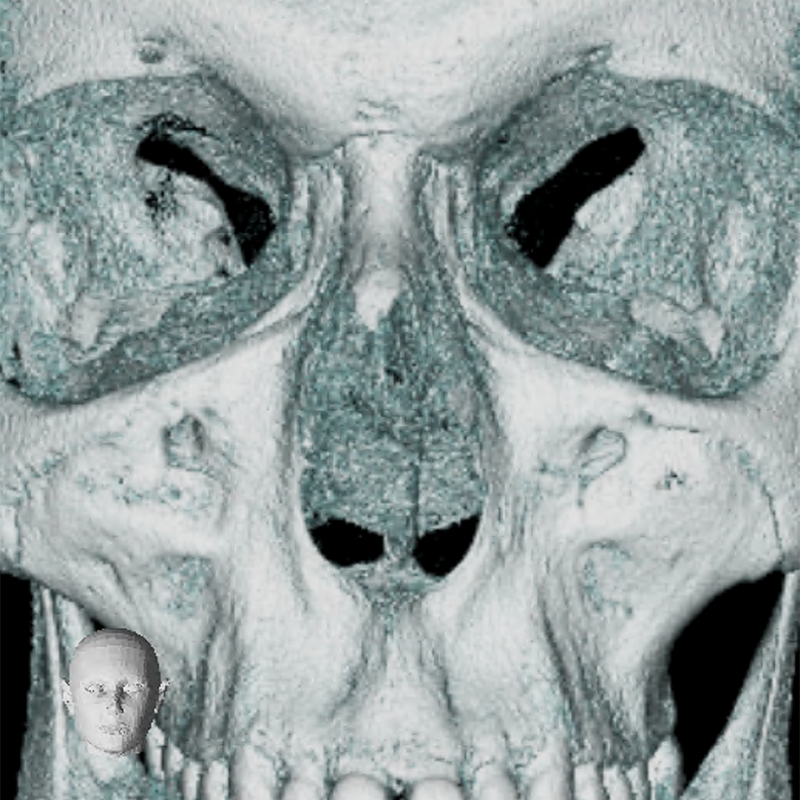

Ihre Praxis für die digitale Volumentomographie (DVT)